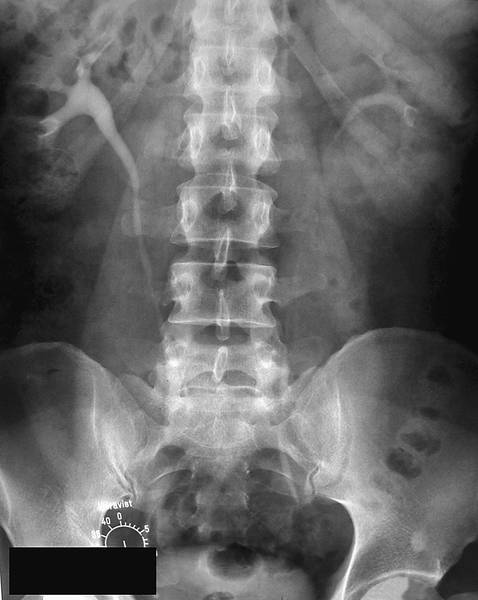

ЭКСКРЕТОРНАЯ УРОГРАФИЯ

Экскреторная урография (Binz, Roseno, 1929) основана на способности почек выделять контрастное вещество, введённое внутривенно (рис.).

Нормальная экскреторная урограмма.

Помимо определения функционального состояния почек, она позволяет получить представление о морфологическом строении мочевыводящих путей, но для этого функция почек должна быть удовлетворительной. По мере её снижения плотность тени контрастного вещества на рентгенограмме также уменьшается. Для проведения экскреторной урографии раствор контрастного вещества вводят в одну из периферических вен. В настоящее время применяют такие жидкие контрастные препараты, как амидотризоевая кислота℘, йогексол, йопромид и йодиксанол. При хорошей функциональной способности почек первую урограмму выполняют спустя 5–7 мин после введения контрастного вещества, у пациентов со сниженной функцией почек — спустя 10–12 мин. Следует обращать внимание на качество урограмм, степень заполнения контрастным веществом разных отделов ВМП, как с правой, так и с левой стороны. В зависимости от результатов первой урограммы последующие снимки выполняют на 15-й и 30-й мин. Если с одной стороны ВМП отчётливо выполнены контрастным веществом, а с другой тень контрастного вещества отсутствует или видна тень расширенных чашечек, то необходимы поздние снимки (через 1–2 ч).

При интерпретации урограмм следует обращать внимание на интенсивность теней паренхимы почек, их величину, форму и положение, начало выделения контрастного вещества в ЧЛС. Кроме того, нужно оценить плотность теней контрастного вещества в лоханках, чашечках и мочеточниках, наличие изменений в ВМП, время поступления контрастного вещества в мочевой пузырь и характер его заполнения. При экскреторной урографии тень рентгенопозитивного камня усиливается. Рентгенонегативный камень даёт дефект наполнения. При нарушении оттока мочи из почки всегда возникает расширение ВМП выше места окклюзии. Наиболее яркая иллюстрация этого — симптом Лихтенберга (рис.), который отмечают при камне мочеточника. Дилатация ЧЛС и мочеточника над камнем напоминает указующий перст, что дало второе название этому симптому — «симптом указательного пальца». Нужно помнить, что абсолютным доказательством камня мочеточника считают обнаружение симптома Лихтенберга на снимках в двух проекциях.